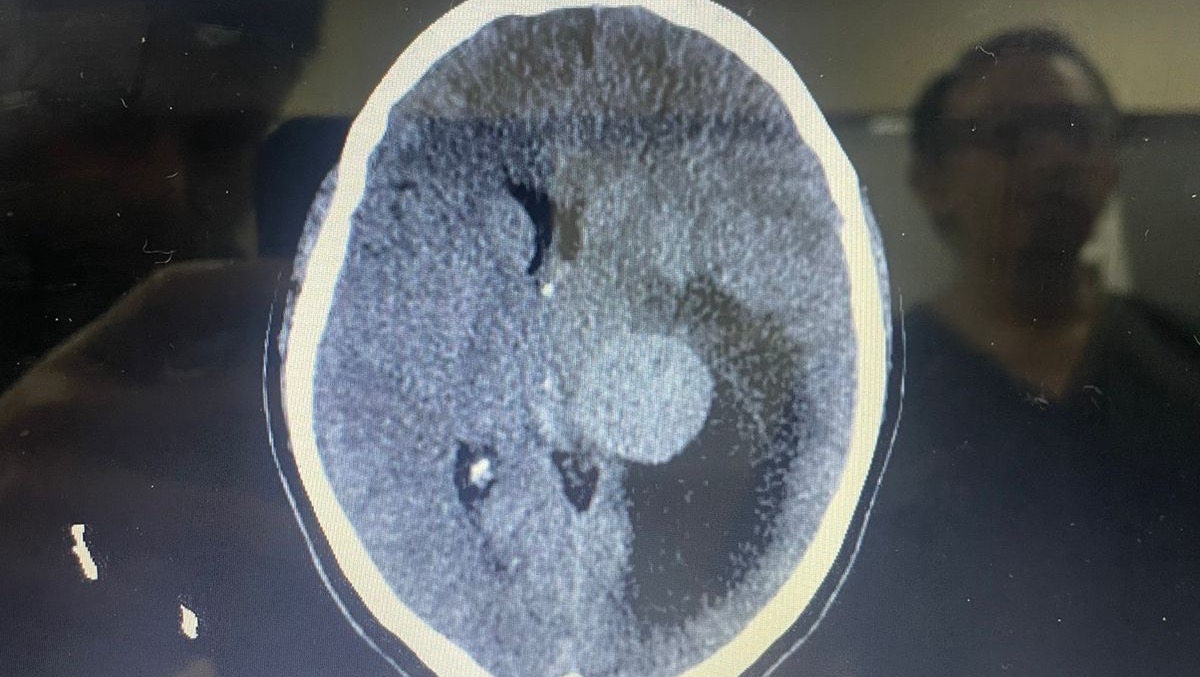

At night I received that call that nobody wants to receive, my mother told me that after medical tests, the result was that she had a very large tumor in the left hemisphere of her brain.

Two days later she had surgery to remove it, the surgery lasted 13 hours.

Por la noche recibí esa llamada que nadie quiere recibir, mi madre me contó que después de los exámenes médicos, el resultado fue que tenía un tumor muy grande en el hemisferio izquierdo de su cerebro. Dos días después la operaron para removerlo, la operación duró 13 horas.